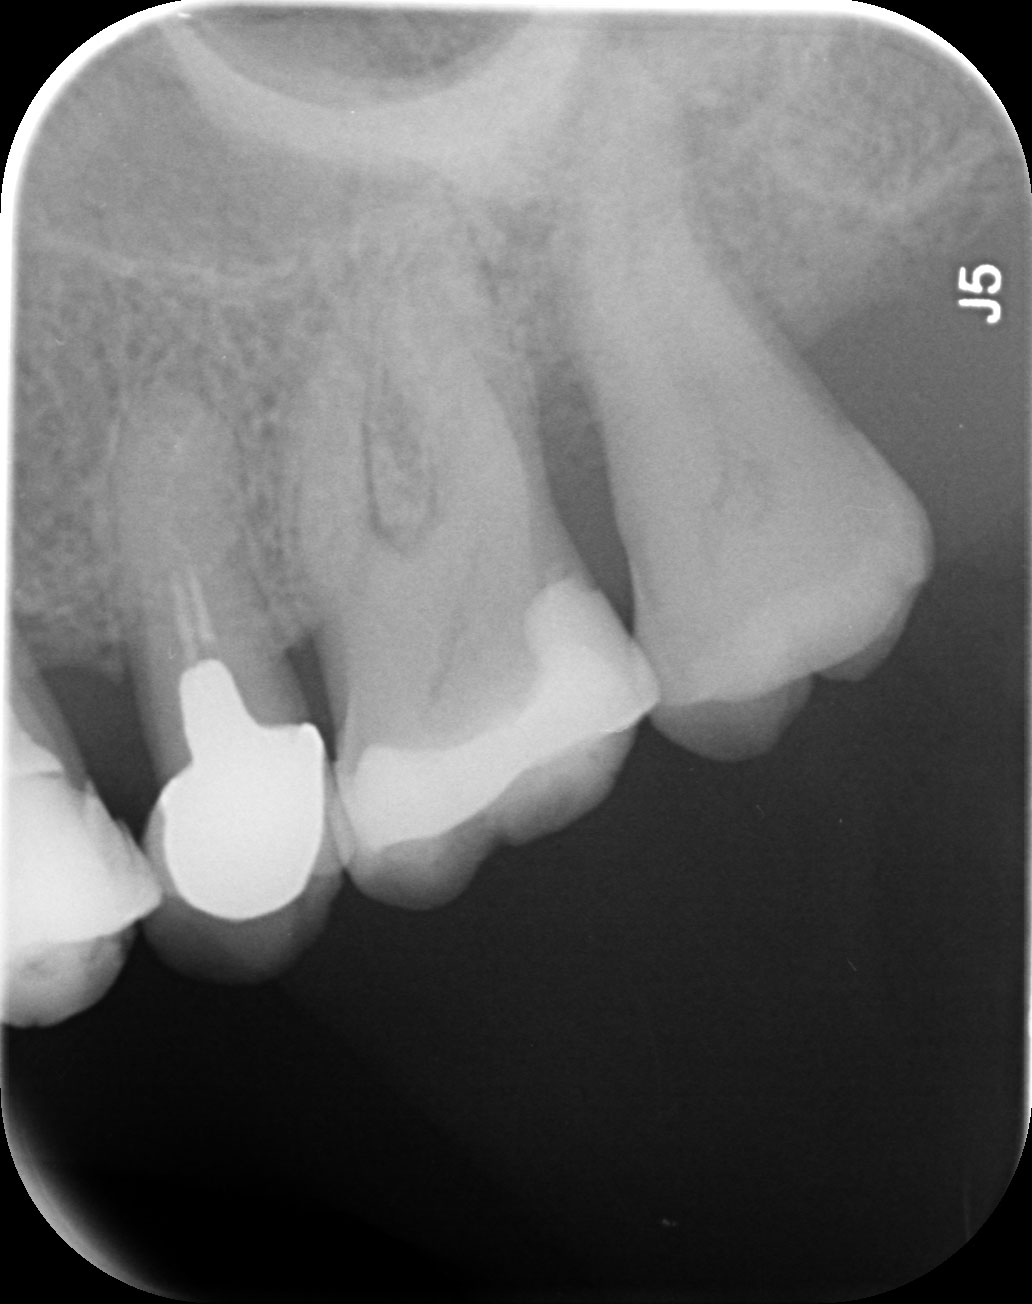

Dantų kanalų gydymas